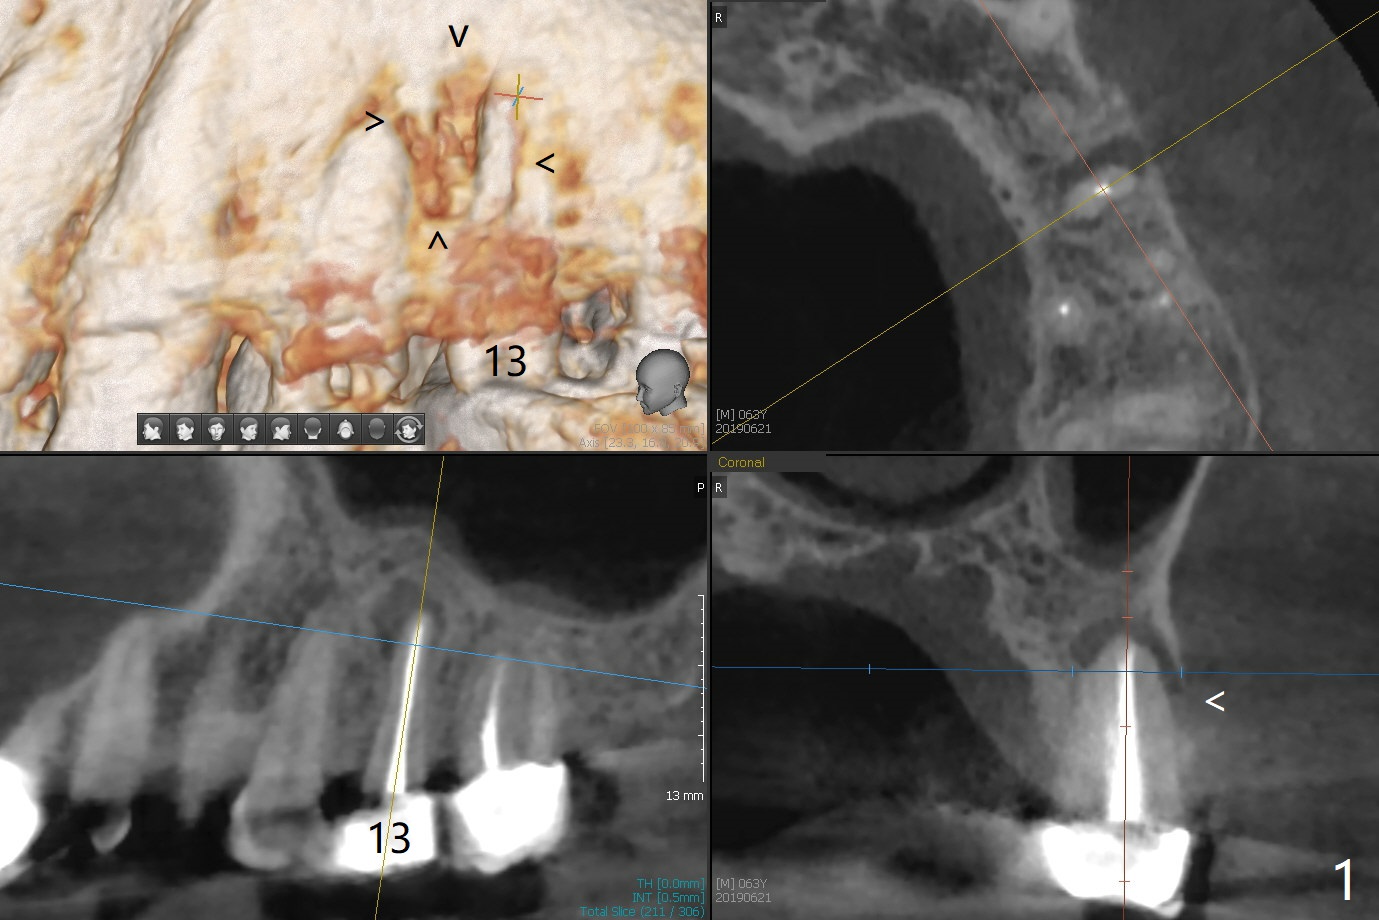

46岁男有多个修复物,左上第二前磨牙时常肿痛(13号牙),根尖阴影大(图一(CT一年前)箭头),根尖颊侧似乎折裂(图二箭头),颊侧牙槽嵴骨质仿佛存在(图三B),即刻种植可行(图四绿色),使用PRF膜(红色)和粘性骨块(黄色)同期修复颊侧骨板缺损。